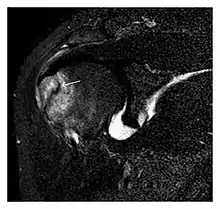

The greater tuberosity of the humerus is also an illustrative location of occult fractures. The osseous injury may follow seizures, glenohumeral dislocation, forced abduction, or direct impaction. They are commonly discovered on MRI in symptomatic patients with suspicion of rotator cuff tear. Coronal images are best suited for detection. They appear as crescentic oblique lines surrounded by a bone marrow edema pattern (Figure 5). The rotator cuff must be inspected since associated ligamentous lesions are common. In the ankle, malleoli and tarsal bones should be checked carefully for any cortical disruptions and radiolucent lines that may reveal a fracture. Awareness of the exact location of the pain will help direct the attention of the interpreter when searching for very subtle signs of fracture (Figure 6).[1]

a

b